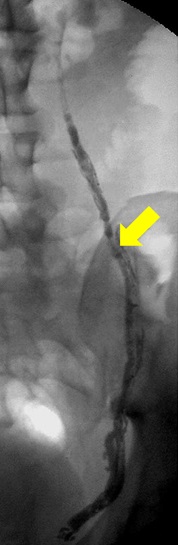

• 4-5F导管 选择性进入卵巢静脉内4-5 F catheter in the ovarian vein

• 评价需要充盈静脉的量 Evaluate the volume required to fill vein

• Valsalva 动作注射30ml Injection of 30 ml performs Valsalva maneuver